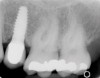

Figure 1  Radiograph demonstrating retained excess cement on abutment (see arrow).

Figure 1